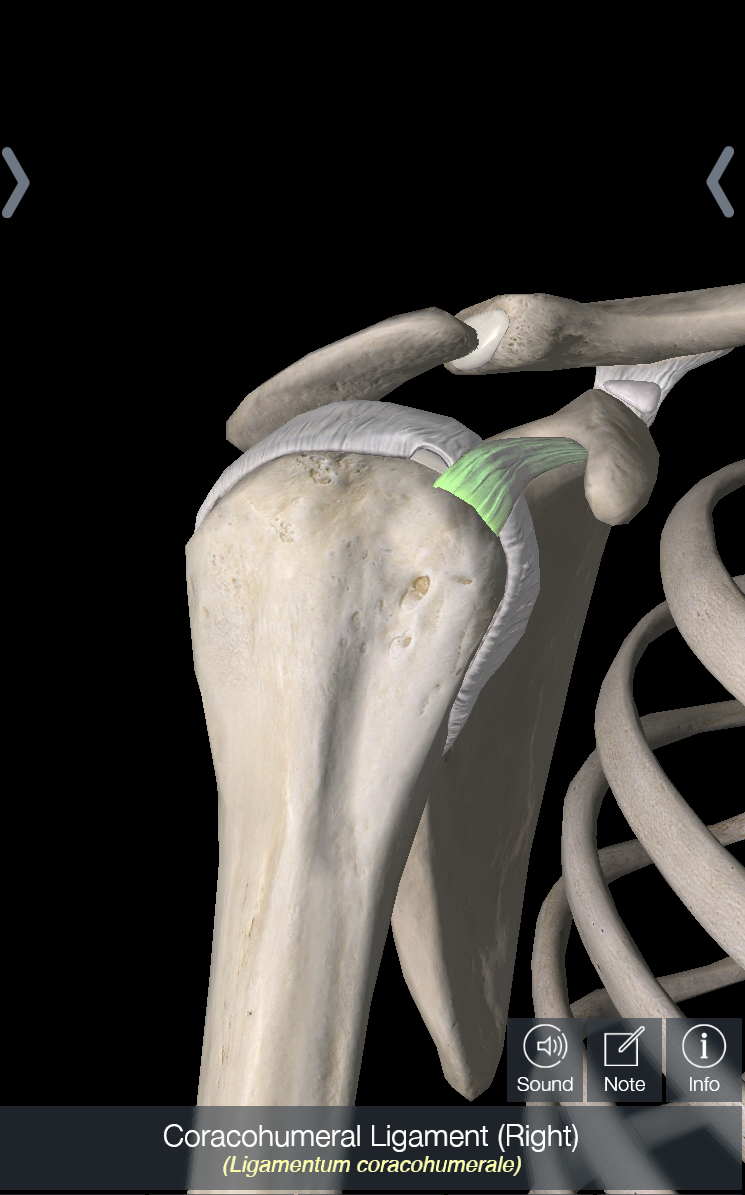

The shoulder joint – also known as the glenohumeral joint – is a ball and socket joint, with a piece of connective tissue called the labrum that surrounds the socket to make the joint more stable. The muscle that is most likely to be torn in an Americana is the subscapularis, which is one of the 4 muscles of the rotator cuff and crosses in front of the shoulder joint. In terms of ligaments, there is a capsule that surrounds the shoulder joint; this can be thought of as a large piece of tissue that surrounds the joint with several areas that are thickened throughout; these are considered ligaments. Of these ligaments – i.e. the ligaments contained within the capsule of the shoulder – the one we care about the most is the inferior glenohumeral ligament (IGHL). In addition, the coracohumeral ligament, which attaches from the front of the scapula to the ball of the shoulder joint, is also important.

In all the pictures below, we are looking at the shoulder from the front. In picture 1, I have removed everything except for the shoulder capsule. In picture 2, I have highlighted the IGHL, which is one of the most stressed ligaments in the shoulder with an Americana. You can imagine that if someone is rotating your shoulder upwards, that will cause this ligament to rotate upwards as well, making it the main part of the capsule being stressed. In picture 3, I have rotated the picture about 60 degrees and highlighted the coracohumeral ligament. And last but not least, in picture 4 I have highlighted the subscapularis.

Why are Americana’s harder to do when your opponent’s elbow isn’t near their side? Two reasons: first, the shoulder has about 30 degrees more motion when it is away from the body compared to when it is by the side; second, the coracohumeral ligament is only stretched when the arm is by the side, and the more ligaments you put pressure on, the more painful it will be.